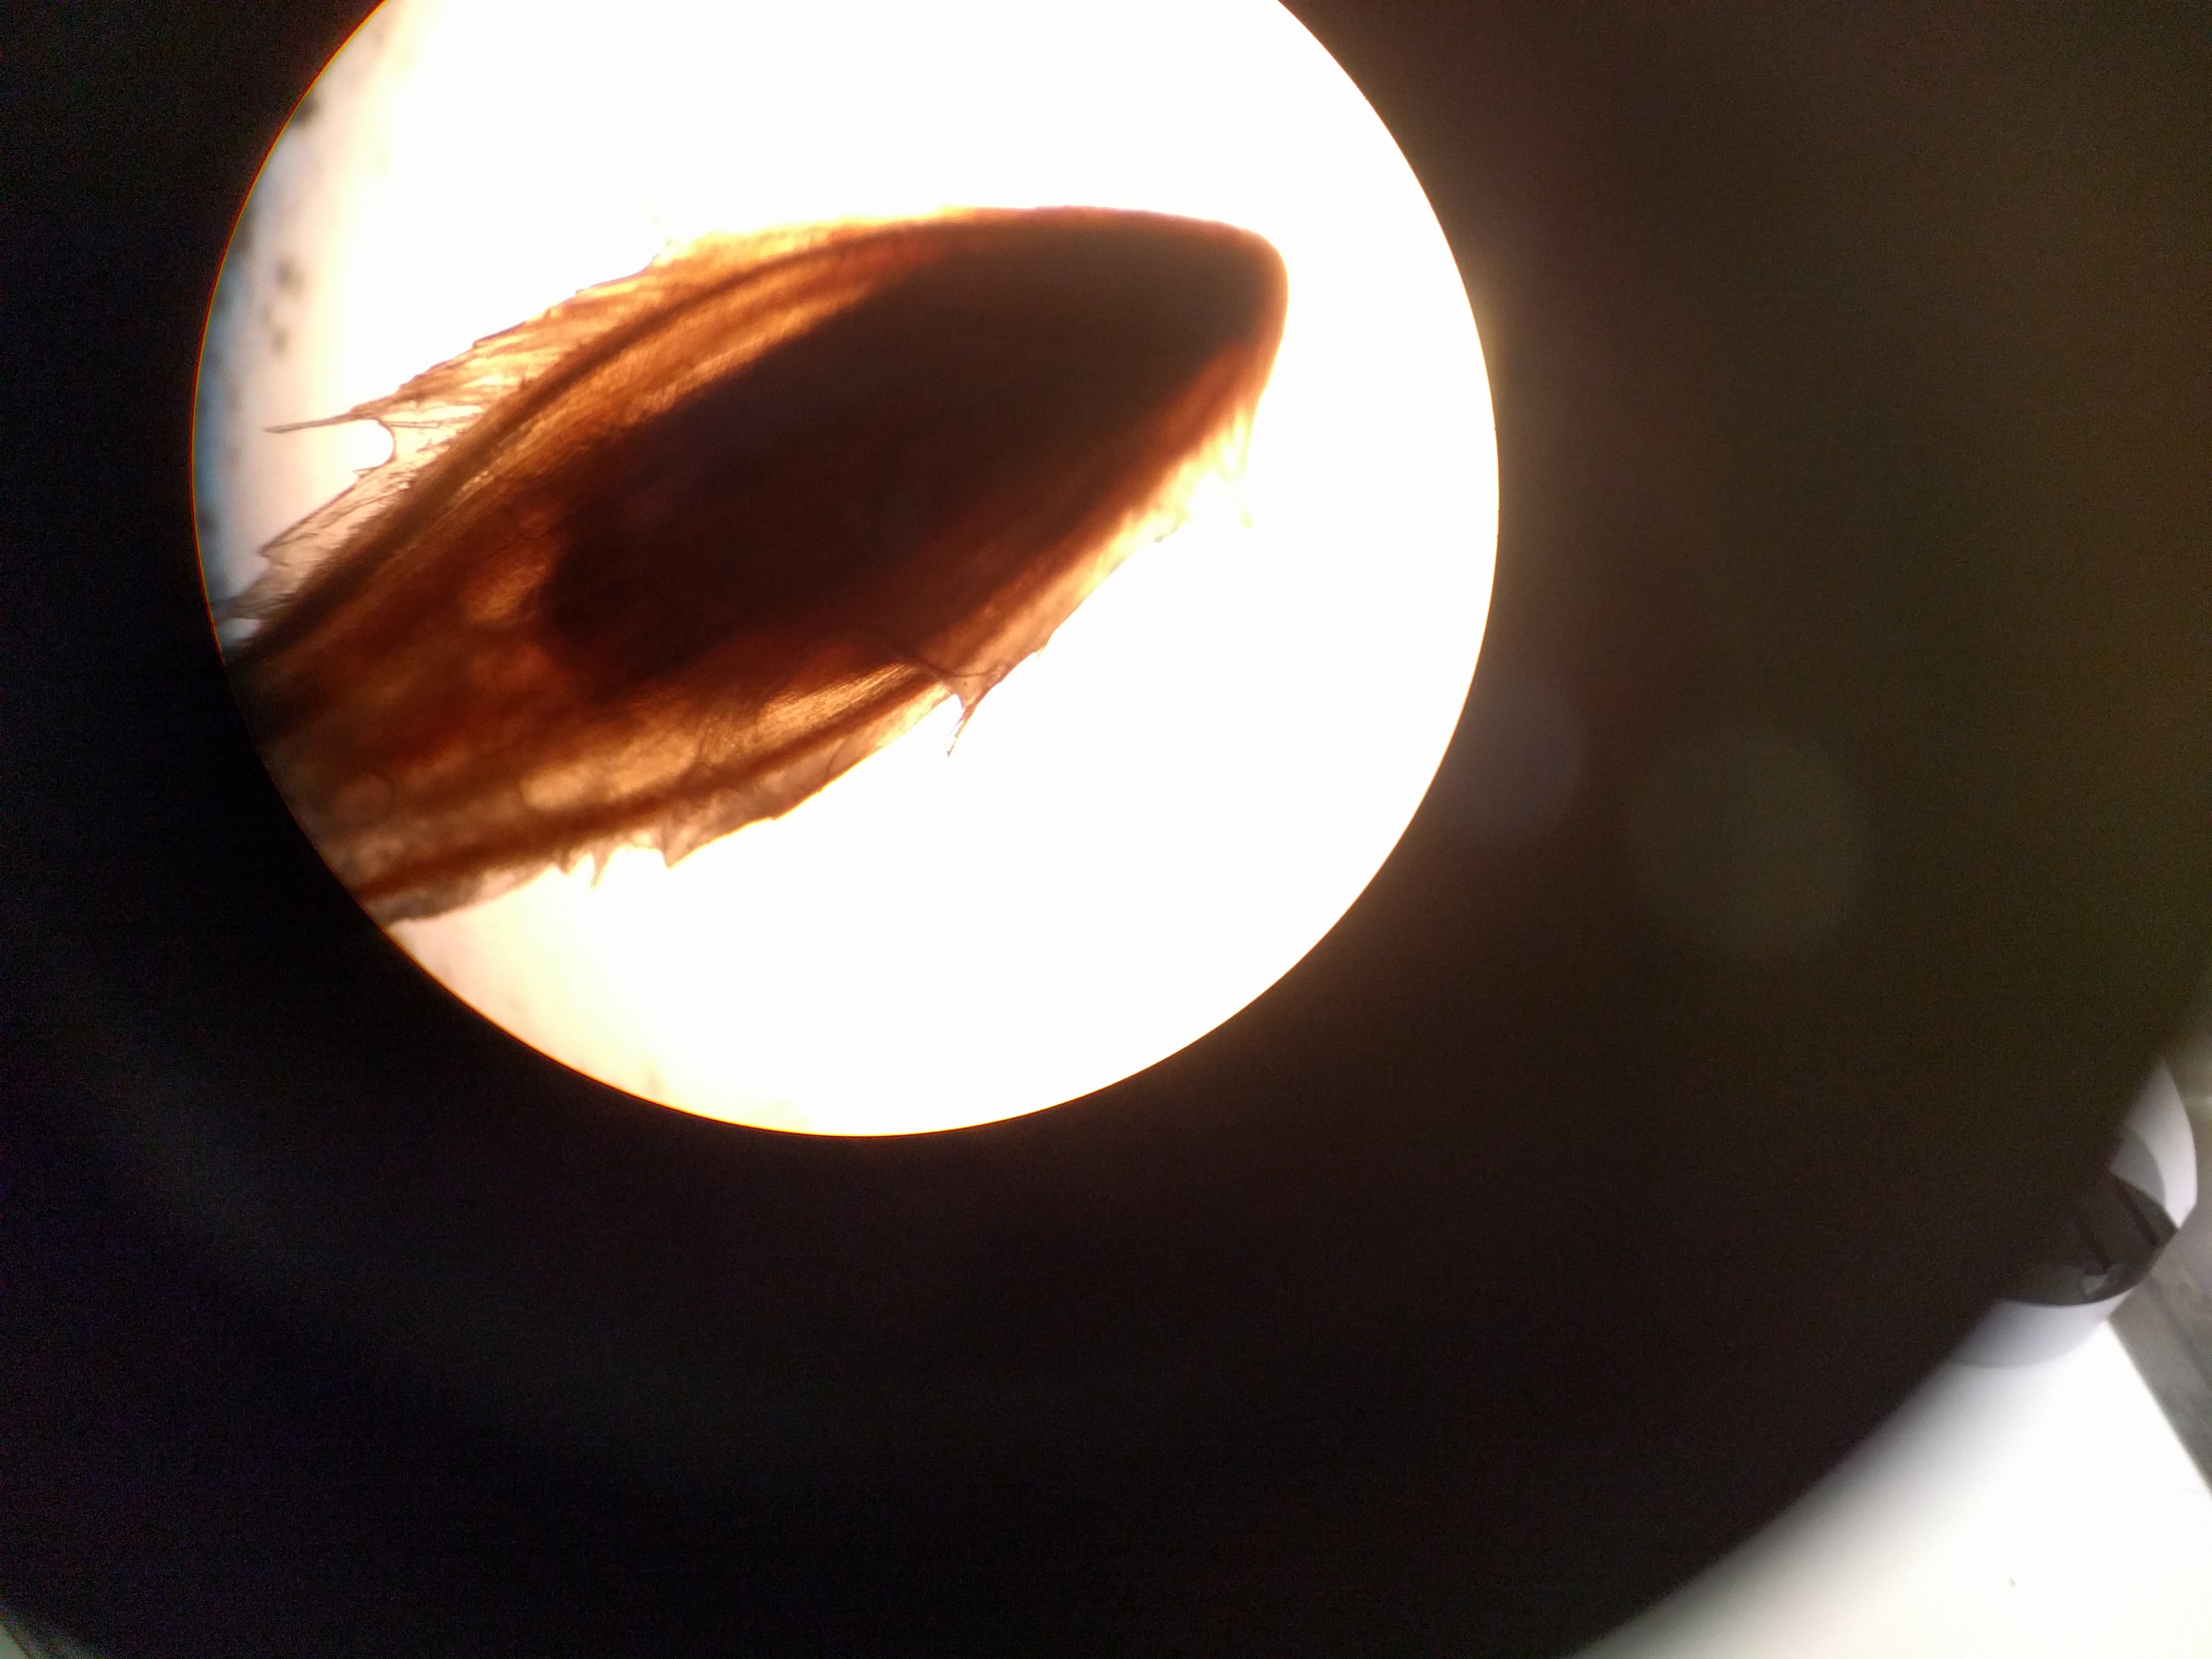

De lastpak onder de microscoop:

aan de linkerkant zit nog een lange venijnige staart (zie hieronder)